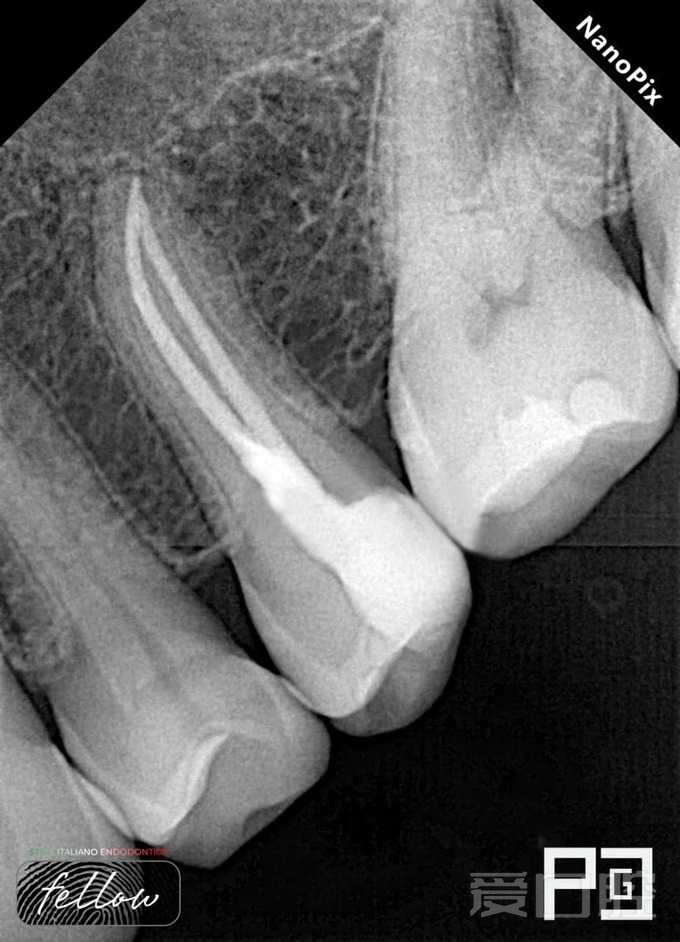

看个根充 —— 上颌第二前磨牙

by Paco CG